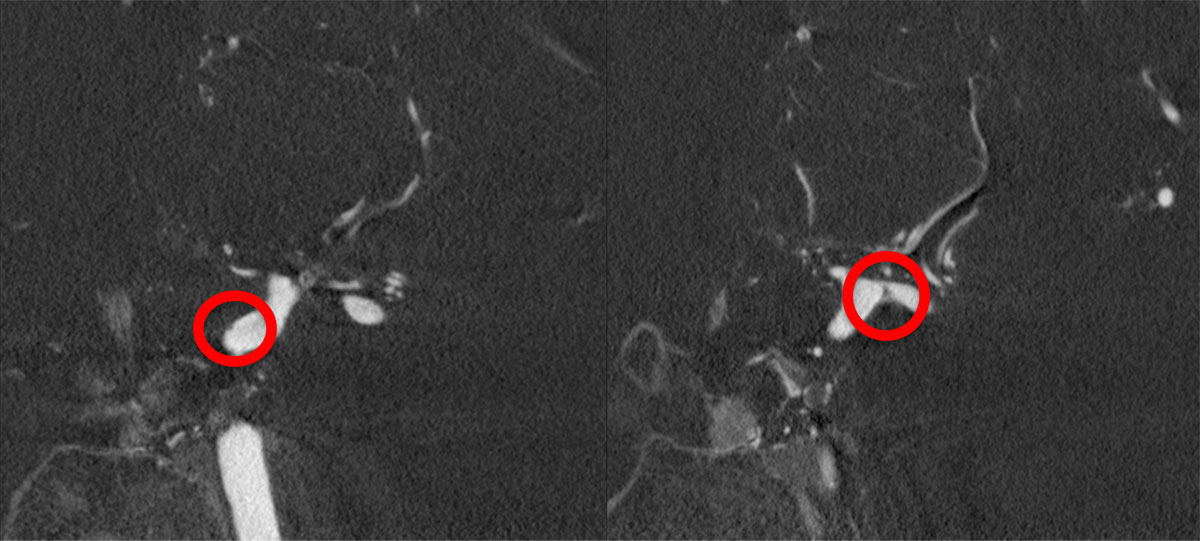

DSA

L - VERT

L - ICA